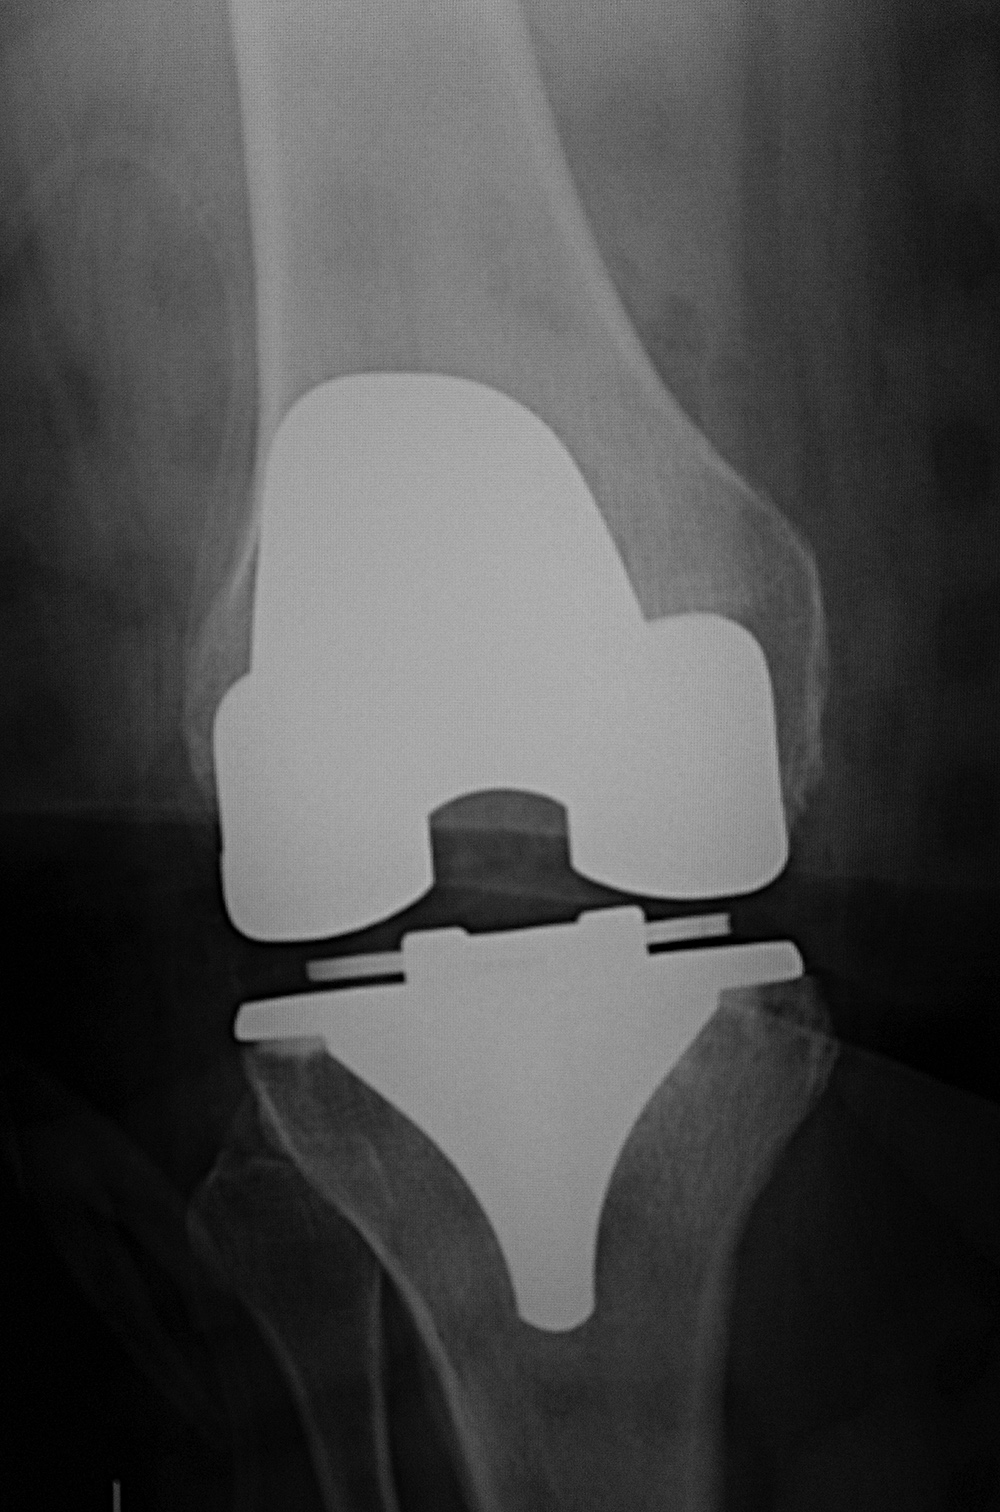

A noncemented total knee arthroplasty is present with a metal backed patellar component. There is also a polyethylene locking clip which locks the tibial polyethylene into the tibial base plate. The anterior cortex of the femur is notched and eroded (top arrow). There is also subtle subsidence of the tibial component (bottom arrow). From Benjamin, 1994 |